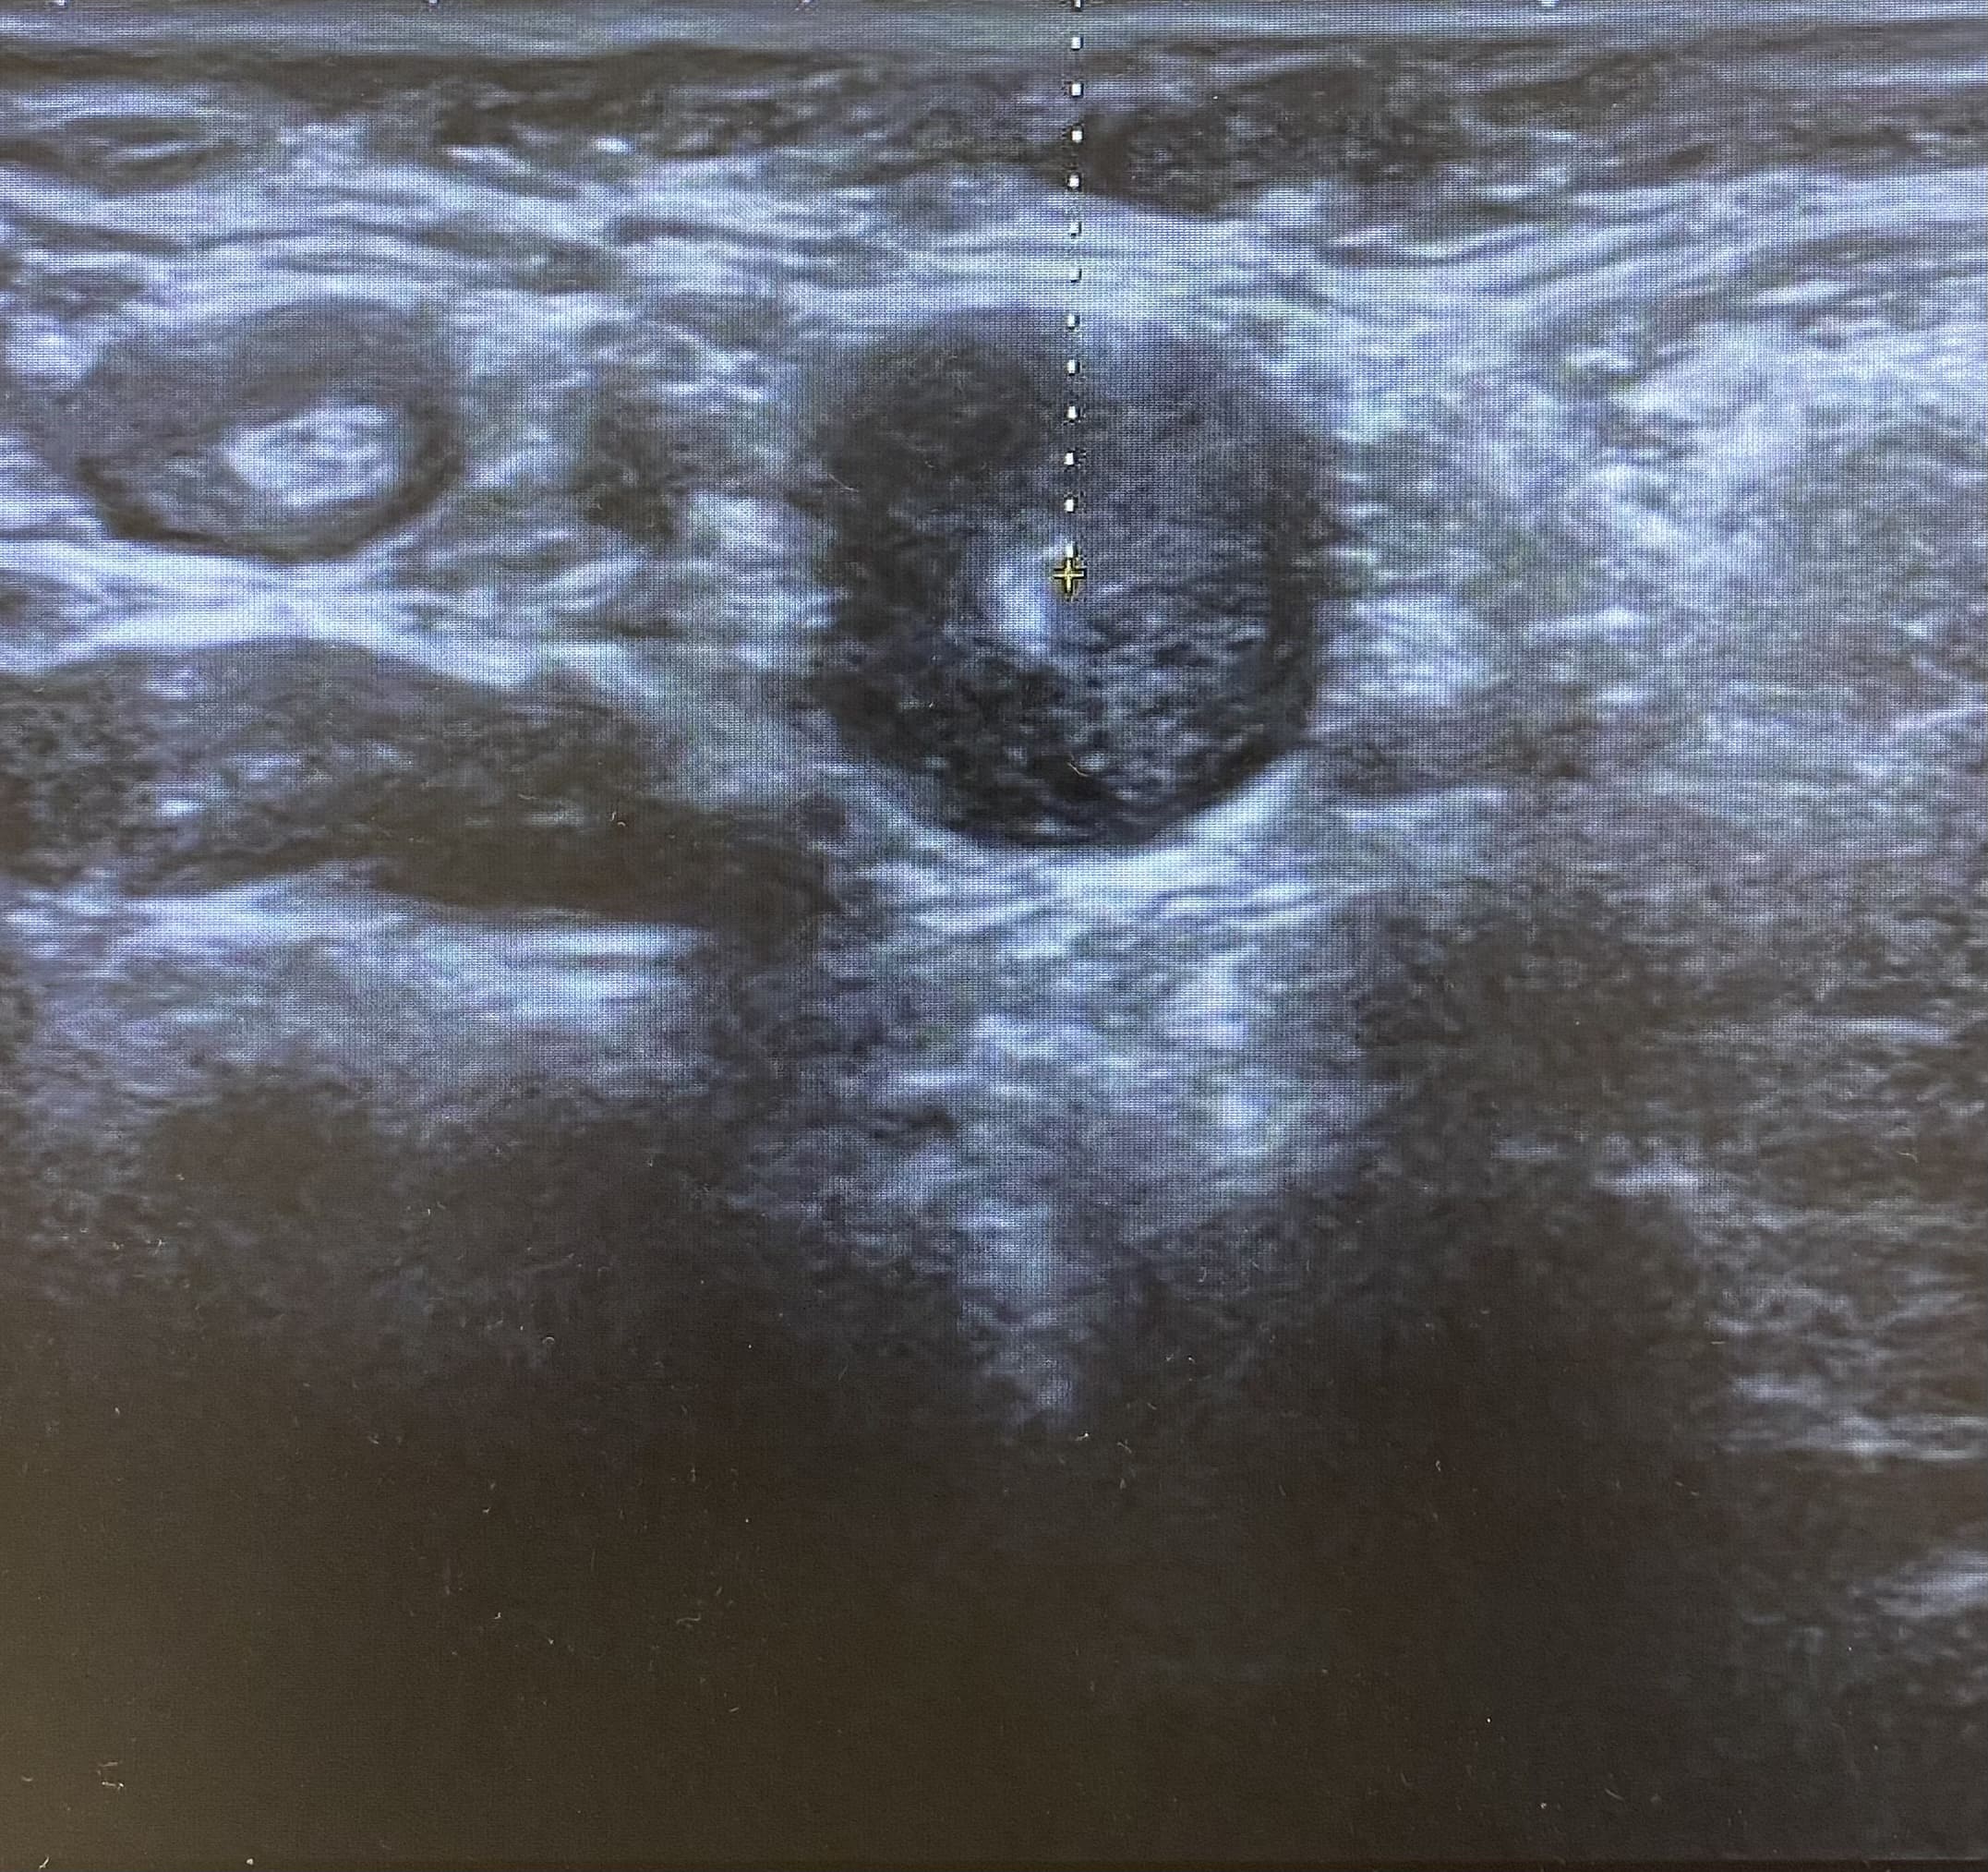

Ecografía: Valoración de adenopatías para acercamiento diagnóstico (típicas/atípicas).

Adenopatías patológicas, algunas redondeadas, con eje anteroposterior > 1 cm, parénquima homogéneo, cortical engrosada aunque con hilio respetado.

Ecografía mamas: quistes y nódulos hipoecogénicos bilaterales.

Ecografía axilar: múltiples adenopatías con eje corto > 2 cm y cortical engrosada.